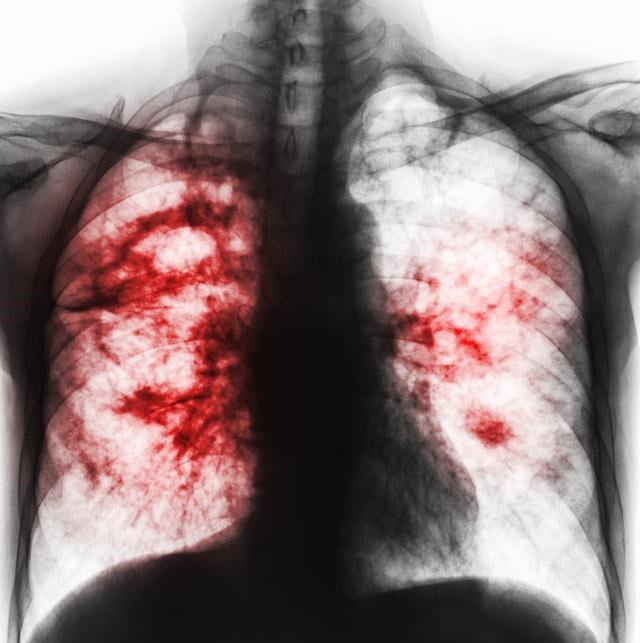

小细胞肺癌在所有肺癌病人中占15-20%,恶性程度高,容易通过血液和淋巴道转移,转移发生早而且广泛。由于小细胞肺癌与其他肺癌有完全不同的特性,因此分期方法有所不同,除了TNM分期,常用美国退伍军人分期标准,分为局限期和广泛期。局限期小细胞肺癌的特点是肿瘤局限于一侧胸腔内,包括有锁骨上或前斜角肌淋巴结转移和同侧胸腔积液。当病变超出局限期范围,均称为广泛期。

小细胞肺癌早期能发现属于比较幸运的,积极规范的治疗部分病人能达到根治的效果,能够长期生存。不过大部分病人即便早期发现,早期治疗,仍可能在2年内出现局部复发或者其他脏器转移,从局限期变成广泛期。这是因为虽然小细胞肺癌对放化疗敏感,但极易发生耐药,其癌细胞倍增时间短,短期内就会出现CT可见的复发转移病灶。